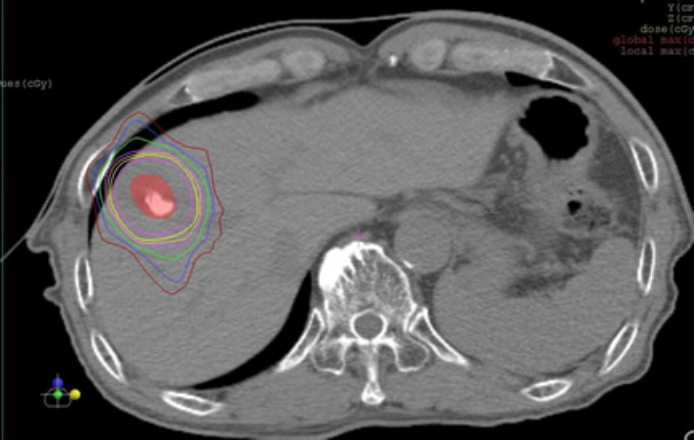

原発性肝がんについてもこの定位放射線治療を行なっております。肺への治療と同様に、図2のように病変に放射線を集中して治療していきます。肺がんにおける位置づけと同様に、外科的治療やラジオ波治療など標準的な治療が難しい場合にこの治療を行うことがあります。可能であれば血管内治療を先行して受けて頂いています。転移性肝がんに対しても可能で、大きさは3cmぐらいまで、当院では過去の治療分も含め合計で1~2回程度までとなります。肝臓の機能が低い、がんが胃腸に近接等の場合は不可能な場合があります。また、患者さんが希望なさいましても他の治療を提案させていただくこともあります。

図2